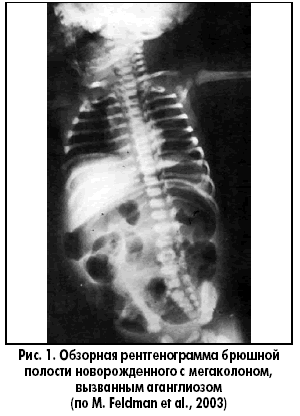

Этот термин часто применяется в связи с болезнью Гиршспрунга, при которой расширение ободочной кишки (рис. 1) происходит вследствие функциональной непроходимости (обычно, прямой кишки), вызванной врожденным отсутствием интрамуральных нервных сплетений (аганглиоз). Аганглиоз приводит к сужению сегмента в дистальных отделах толстой кишки, т. е. этот сегмент не способен к расслаблению. Болезнь Гиршспрунга может сопутствовать многим нарушениям, в том числе и множественной эндокринной неоплазии (МЭН) типа IIb.

Патогенез. Считается, что аганглиоз толстой кишки возникает вследствие остановки каудальной миграции клеток нервных отростков, которые должны развиться в интрамуральные нервные сплетения кишки. Это приводит к нейронной дисплазии, гипоганглиозу и сегментарному аганглиозу. Обычно аганглиозный сегмент находится в прямой и/или сигмовидной кишке. Реже этот сегмент очень короткий и локализуется только в зоне анального сфинктера. Аганглиозный сегмент постоянно находится в состоянии спазма, что приводит к супрастенотическому расширению в проксимальной части кишки. Аганглиозный сегмент большей длины встречается примерно у 20% больных. Случаи распространения такого сегмента на всю ободочную кишку встречаются нечасто, а более проксимальное распространение аганглиоза на всю тонкую кишку наблюдается еще реже. Таким образом, отличительным признаком при диагностике болезни Гиршспрунга является исчезновение ганглиоцитов из нервных сплетений мышечной оболочки и подслизистой основы кишечника, о чем свидетельствуют данные аспирационной или прицельной биопсии. Пассаж содержимого кишки над аганглиозным сегментом задерживается. Хотя более длинные аганглиозные сегменты дают более яркую картину заболевания, состояние некоторых больных с короткими аганглиозными сегментами также может прогрессивно ухудшаться.